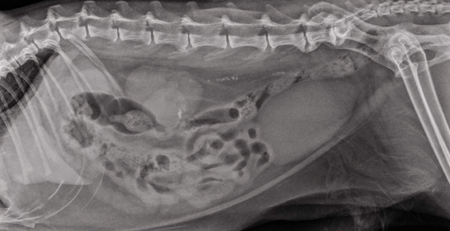

En este artículo se ofrece un enfoque a la radiología a partir de un estudio de caso con el objetivo de mostrar...

Tanto los corticosteroides como los antiinflamatorios no esteroideos (AINEs) son conocidos por sus efectos adversos.